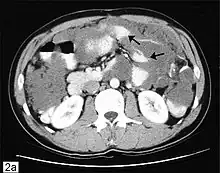

| Computed tomographic scan of an abdomen showing pseudomyxoma peritonei with multiple peritoneal masses (arrow) with "scalloping effect" seen. | |